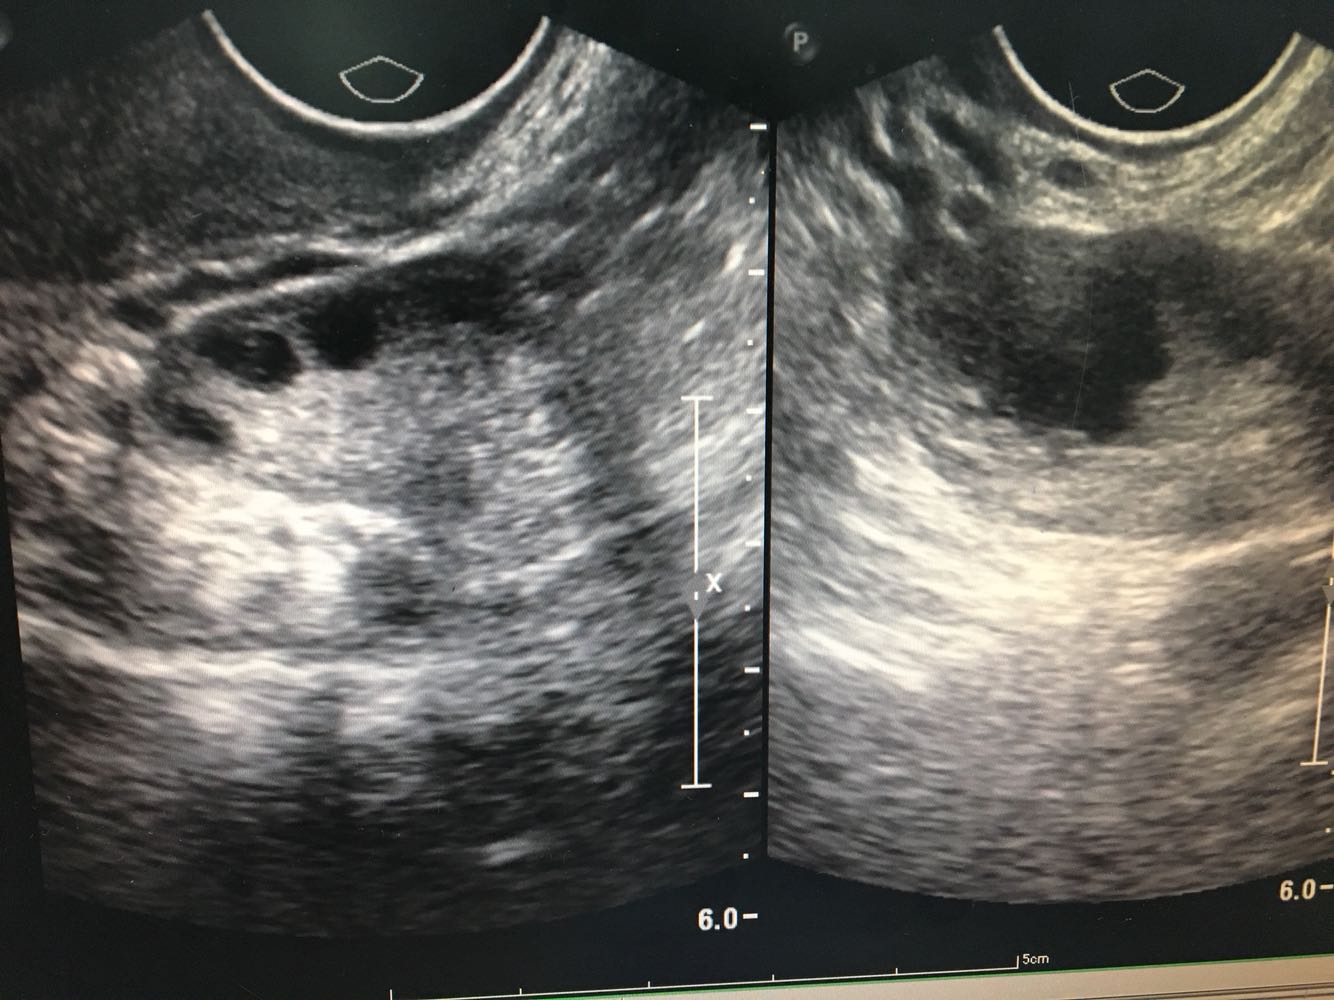

1.患者,女,35岁     2.主诉:人流后经量减少伴痛经7月余 3.现病史:0-0- 2-0,初潮14岁,既往5/25,经量中等,无痛经。患者于2016年12月行人工流产术,术后1月月经正常来潮,2017年1月起出现明显经量减少,经期缩短伴下腹坠痛,自行服用中药调理(具体药物不明),未见明显好转。2017年4月就诊外院,B超诊断为宫颈粘连(报告未见),当时未予特殊处理。患者经量仍有减少,经期缩短至1天,腹痛症状逐渐加重,无腹泻,无恶心呕吐,无畏寒发热等不适。遂就诊我院B超示子宫内膜回声不均匀,宫腔部分粘连可能;小型子宫肌瘤;盆腔积液;右附件系膜囊肿。现患者有生育要求,为寻求进一步治疗,拟“人工流产后宫腔粘连”收治入院。病程中患者无异常阴道流血流液,无经期间出血,无发热,无恶心呕吐。

诊断: 流产后宫腔粘连(可能);子宫平滑肌瘤(小型) 诊疗方案:患者入院后完善各项检查,麻醉下行宫腔镜下宫腔粘连分解+刮宫术,术中见:宫颈管形态正常,宫腔上1/3宫底处粘连,左右两侧壁膜状轻度粘连,双侧输卵管未见。以剪刀剪开宫底处粘连使宫底处展平,暴露双侧输卵管开口清晰,剪除左右两侧壁膜状粘连带,使宫腔恢复正常形态。刮匙沿宫腔四壁轻柔搔刮,刮出少量内膜送病理。手术顺利,术后给予抗炎治疗,观察阴道出血少,患者生命体征平稳。